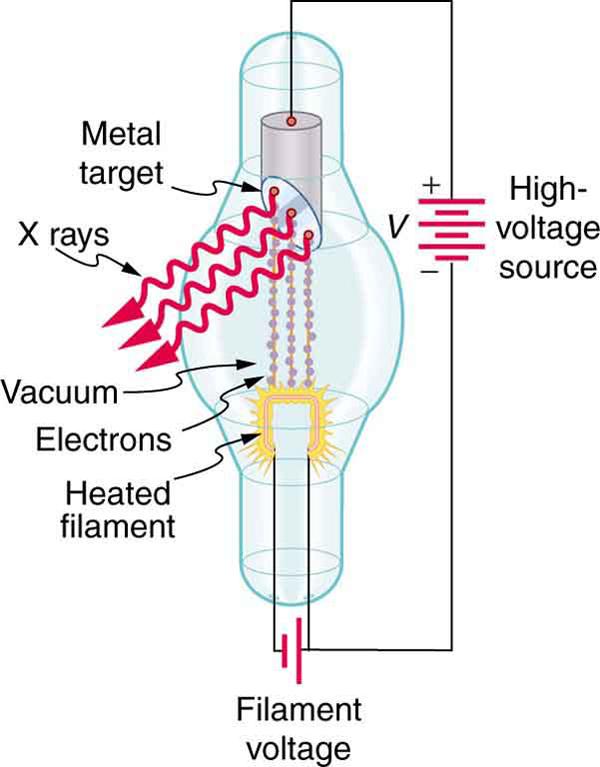

While rays originate in nuclear decay, X-rays are produced by the process shown in Figure 12.13. Electrons ejected by thermal agitation from a hot filament in a vacuum tube are accelerated through a high voltage, gaining kinetic energy from the electrical potential energy. When they strike the anode, the electrons convert their kinetic energy to a variety of forms, including thermal energy. But since an accelerated charge radiates EM waves, and since the electrons act individually, photons are also produced. Some of these X-ray photons obtain the kinetic energy of the electron. The accelerated electrons originate at the cathode, so such a tube is called a cathode ray tube (CRT), and various versions of them are found in older TV and computer screens as well as in X-ray machines.

Find the maximum energy in eV of an X-ray photon produced by electrons accelerated through a potential difference of 50.0 kV in a CRT like the one in Figure 12.13.

This example produces a result that can be applied to many similar situations. If you accelerate a single elementary charge, like that of an electron, through a potential given in volts, then its energy in eV has the same numerical value. Thus a 50.0-kV potential generates 50.0 keV electrons, which in turn can produce photons with a maximum energy of 50 keV. Similarly, a 100-kV potential in an X-ray tube can generate up to 100-keV X-ray photons. Many X-ray tubes have adjustable voltages so that various energy X-rays with differing energies, and therefore differing abilities to penetrate, can be generated.